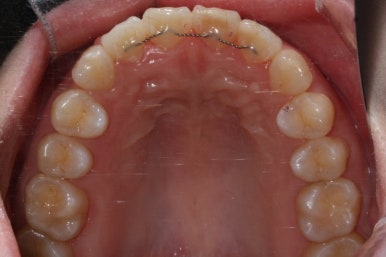

어쨌든, 앞니는 가지런하게 마무리가 잘 되었고, 앞니 안쪽에는 유지철사를 부착하고 치료를 종료하였습니다.

부산앞니교정 키다리아저씨치과에서 시행한 이번 MTA 부분교정의 전후 비교입니다.

위아래 앞니가 가지런해졌고, 작은 앞니의 얼룩무늬도 없어졌네요.